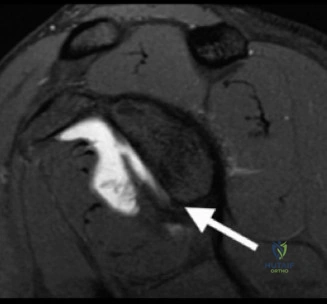

The concept of the Glenoid Track is essential for understanding bipolar bone loss. The glenoid track is the contact zone of the glenoid on the posterior humeral head as the arm moves through its range of motion. If a Hill-Sachs lesion extends medial to the glenoid track, it is classified as "off track" and will engage the anterior glenoid rim, levering the humeral head out of the joint. Glenoid bone loss narrows the glenoid track, making a previously "on track" Hill-Sachs lesion "off track."

The en face view of the glenoid on 3D CT with the humeral head digitally subtracted allows for precise measurement. The "best fit circle" method is commonly utilized. A circle is drawn matching the contour of the inferior and posterior glenoid, and the area or width of the missing anterior bone is calculated relative to the area or diameter of the circle. The Pico method compares the surface area of the injured glenoid to the contralateral normal glenoid, assuming the contralateral shoulder is uninjured. The humeral head must also be evaluated to calculate the glenoid track, measuring the width of the Hill-Sachs lesion and the intact anterior glenoid bone bridge.

The Glenoid Track concept, detailed by Di Giacomo, Itoi, and Burkhart in 2014, revolutionized the understanding of bipolar bone loss. They provided a biomechanical framework to determine whether a Hill-Sachs lesion would engage the anterior glenoid rim based on the width of the intact glenoid. This concept shifted the focus from isolated glenoid or humeral defects to the dynamic interplay between the two surfaces, guiding the use of the remplissage procedure for off track lesions with subcritical glenoid bone loss.